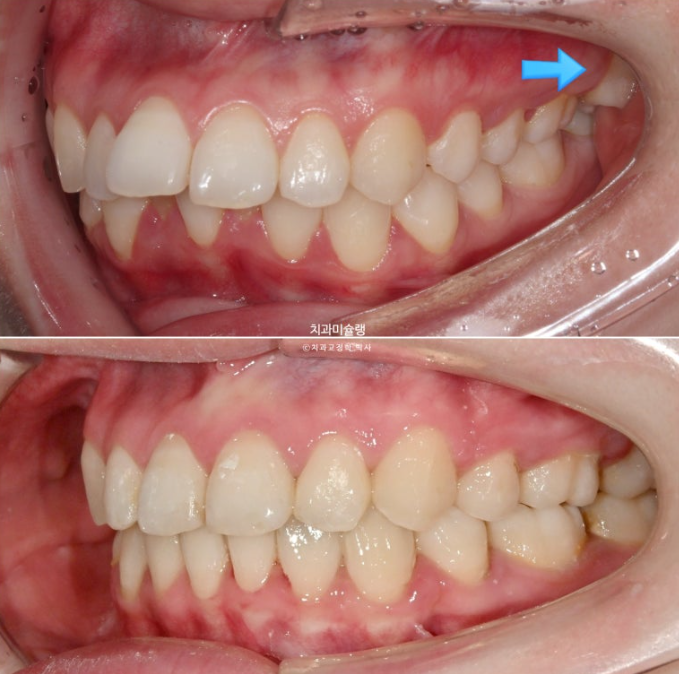

위 아래 중심선은 어긋나 있고

윗니가 아랫니를 많이 덮어 아랫니가 잘 안보이는 심한 과개교합이 보입니다.

파란 화살표 부분은 위 아래 큰어금니가 엇갈려 물리는 가위교합입니다.

파란화살표 두번째 큰어금니가 바깥으로 밀려나가 가위교합이 된 것 입니다.

앞니도 많이 삐뚤합니다.

파란 화살표 큰어금니가 입천장쪽으로 들어오면서 가위교합이 해소가 되었습니다.

어긋나 있던 중심선은 정확히 맞으며 깊게 물리는 과개교합이 해소되어 이제 아래 앞니가 정상적으로 보입니다.

뿐만 아니라 치아 높낮이 불규칙으로 인해 들쑥날쑥 했던 아래 앞니가 배열되면서 잇몸라인도 어느정도 정리가 되었습니다.

파란 화살표 부분의 가위교합이 개선이 되면서 어금니 교합은 물샐틈 없는1급 교합관계를 보입니다.